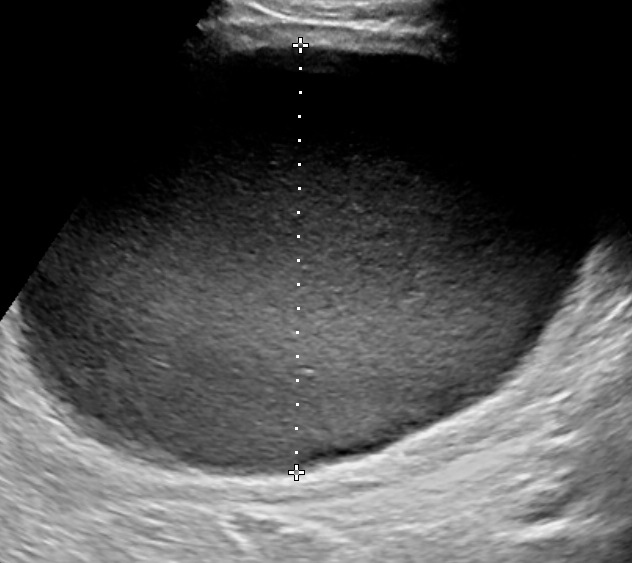

The gestational week does not influence the diagnosis of polyhydramnios. The size of the uterus could be suggesting of this condition, however the diagnosis should be made during ultrasound examination. There are two common ways to estimate the volume of the amniotic fluid:

- Single Deepest Pocket (SDP). A vertical measurement in the deepest amniotic fluid pocket. Values below 2 cm indicate oligohydramnios, values over 8 cm indicate polyhydramnios (8-11: mild, 12-15: moderate, > 16: severe). In multiple gestation, a range of 3–8 cm is defined as normal. Another technique is the

- Amniotic Fluid Index (AFI). This is the sum of vertical measurements of all four quadrants (polyhydramnios usually >24).